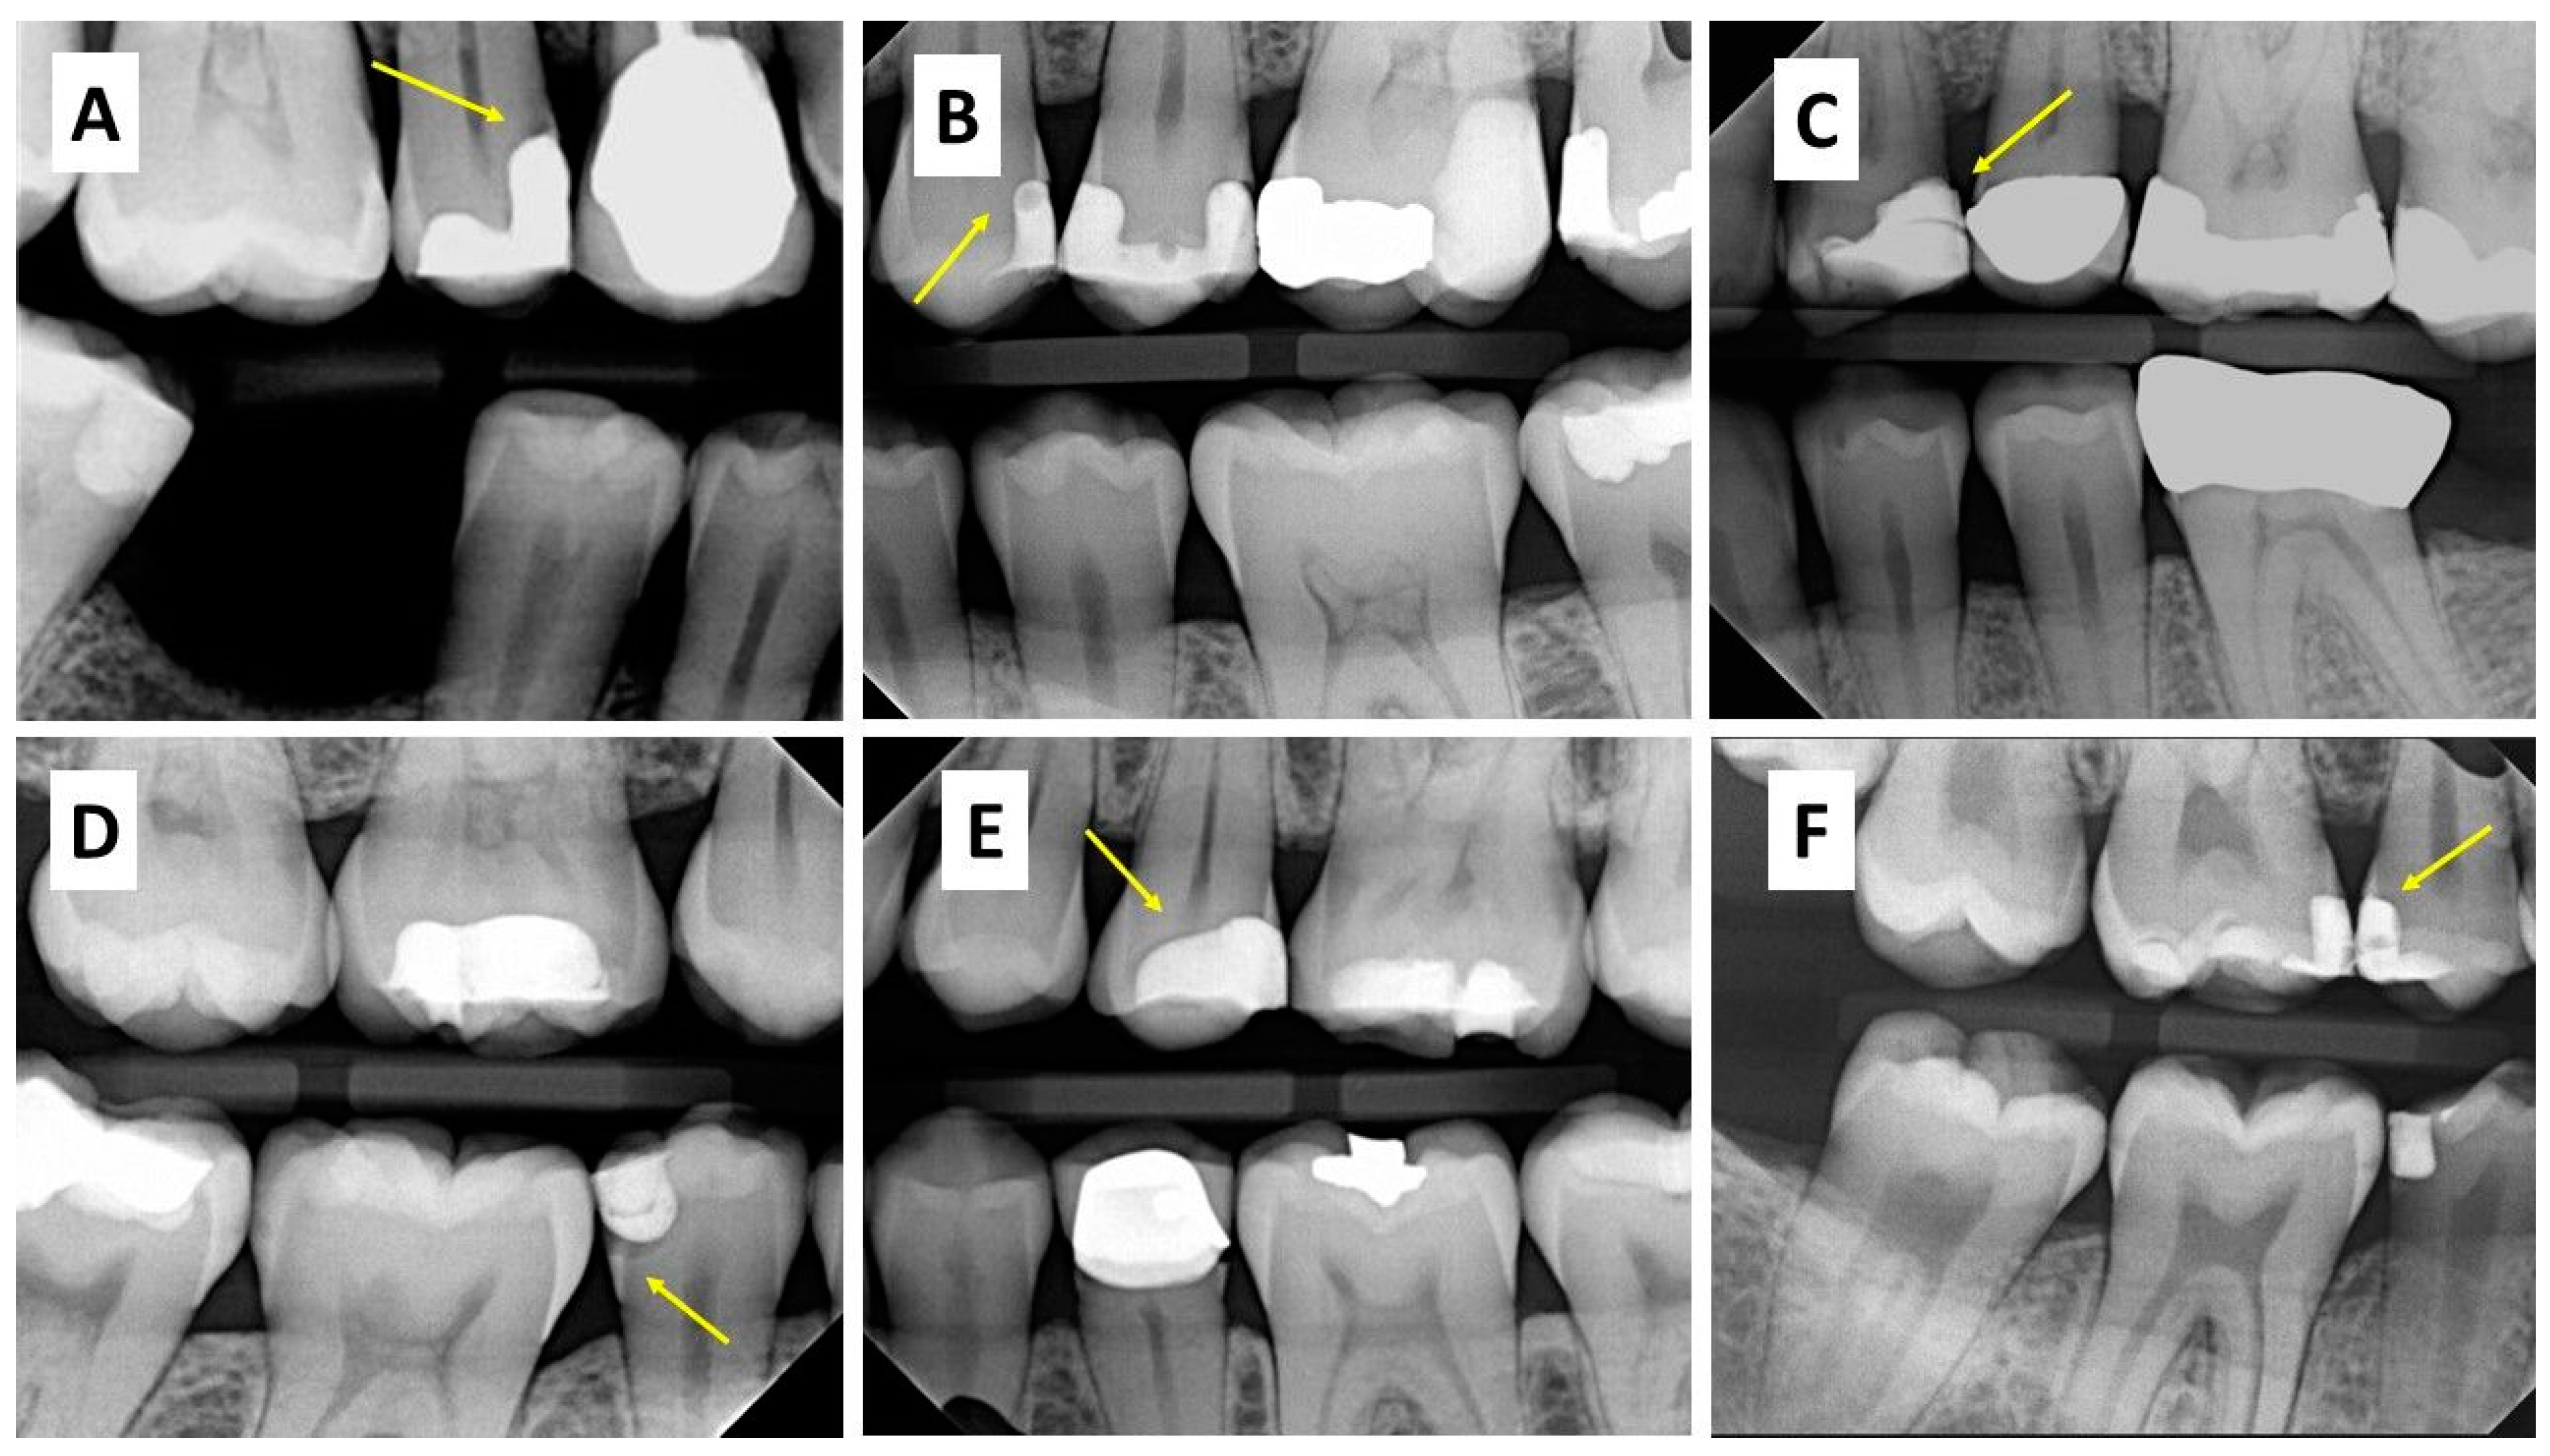

Noncavitated dental radiolucent lesions A challenge for the dental What Does Non Radiolucent Mean Structures that are cavities, depressions, or openings in bone such as a sinus, fossa, canal or foramen will allow x. A radiopaque structure has high. It’s often used in the context of. A radiolucent structure has low density and will result in a black color on the radiograph. Areas that are less dense, such as something containing gas, will allow. What Does Non Radiolucent Mean.

Noncavitated dental radiolucent lesions A challenge for the dental What Does Non Radiolucent Mean A radiopaque structure has high. A radiolucent structure has low density and will result in a black color on the radiograph. Lucency is a term that refers to the quality of being transparent or allowing light to pass through. Areas that are less dense, such as something containing gas, will allow more xrays through, appear darker on the radiograph, and. What Does Non Radiolucent Mean.